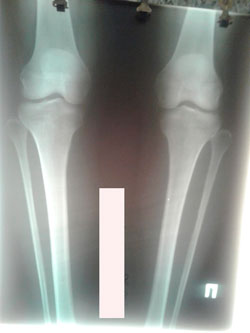

Исходник - 31 год. Бишкек.

Дата операции - 02.11.2020

Диагноз: Варусная деформация обеих голеней + Ротация с обеих сторон.